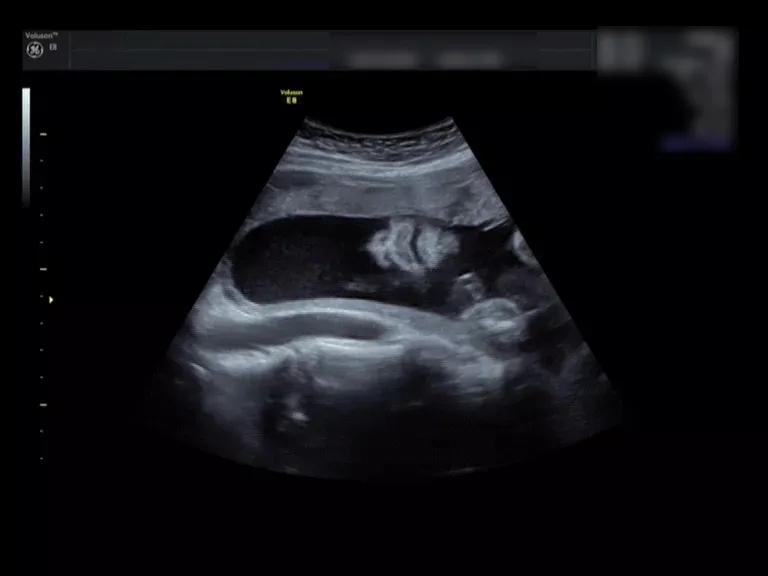

来看这个小baby的彩超对比

就一目了然啦

(二维超声)

(三维超声)